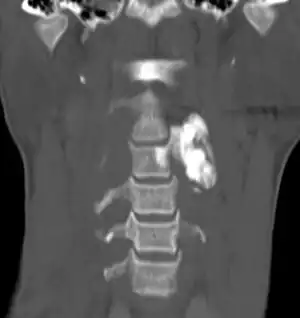

| Osteoblastoma in neck | |

Generaly, osteoblastomas present between the age of 20 and 40 years.[4] Around 40% are located in the spine, and over half have associated scoliosis.[4]

When diagnosing osteoblastoma, the preliminary radiologic workup should consist of radiography of the site of the patient's pain. However, computed tomography (CT) is often necessary to support clinical and plain radiographic findings suggestive of osteoblastoma and to better define the margins of the lesion for potential surgery. CT scans are best used for the further characterization of the lesion with regard to the presence of a nidus and matrix mineralization. MRI aids in detection of nonspecific reactive marrow and soft tissue edema, and MRI best defines soft tissue extension, although this finding is not typical of osteoblastoma. Bone scintigraphy (bone scan) demonstrates abnormal radiotracer accumulation at the affected site, substantiating clinical suspicion, but this finding is not specific for osteoblastoma.

It usually presents in the vertebral column or long bones.[9][10] The tumors usually involve the posterior elements, and 17% of spinal osteoblastomas are found in the sacrum. The long tubular bones are another common site of involvement, with a lower extremity preponderance. Osteoblastoma of the long tubular bones is often diaphyseal, and fewer are located in the metaphysis. Epiphyseal involvement is extremely rare. Although other sites are rarely affected, several bones in the abdomen and extremities have been reported as sites of osteoblastoma tumors.